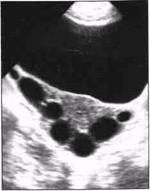

2. Многокамерный вариант.

Локализация такая же, как и при первом варианте, но с большим распространением в латеральном и медиальном направлениях за счёт более крупных размеров патологического очага и часто встречающегося двухстороннего поражения. На эхограммах (условия сканирования прежние, с элементами продольной эхолокации) в одной из параметральных областей с распространением в позадиматочное пространство лоцируется многокамерное жидкостное образование неправильной вытянутой формы, которая зависит от числа камер и степени распространенности процесса. Многокамерность образования обусловлена множественными перетяжками, возникающими либо вследствие перегибов маточной трубы, заполненной воспалительным экссудатом, либо за счет спаек, частично или полностью перекрывающих просвет трубы. Число камер (полостей) колеблется от 2 до 7. Стенки тонкие, контуры чёткие и неровные из-за выпячивания перерастянутых жидкостью стенок маточной трубы. Размеры варьируют в широких пределах, но во всех случаях длина гидросальпингса значительно больше его поперечника. В некоторых наблюдениях длина жидкостного образования достигает 150 мм. Структура содержимого однородная. Крайне редко в одной из полостей видны мелкие эхопозитивные включения линейной формы, низкой эхоплотности (фибрин, детрит), хорошо видимые при ТВ-сканировании. В отличие от других патологических многополостных жидкостных образований встречающихсяв малом тазу, для многокамерного гидросальпингса характерно своеобразное расположение составляющих его камер - друг за другом, как звенья цепи. Этот симптом не может считаться патогномоничным, но безусловно является постоянным эхо-признаком данного вида экссудативного сальпингита. Матка не изменена. Яичник на стороне поражения не лоцируется, так как параметральная область и позадиматочное пространство, как правило, полностью заняты патологическим жидкостным объектом. Другой яичник без особенностей.